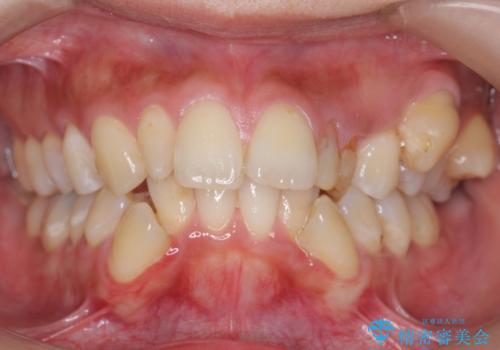

- 前歯のならびを主訴に来院。

がたがたが多く、口元も出せないためやむなく抜歯しましたが、その際、通常は上は前から4番目の歯を抜くところを、左右とも金属の詰め物がある5番目の歯を抜いて治療しました。

そこを天然の歯を残し、すでに削ってある5番目の歯を抜歯した上で、口元も改善し、治療期間を4番目を抜いたのと変わらない(20代の大人で抜歯ではむしろ短い)期間で終了することができました。

また、矯正用ミニスクリューも用いて、できる限り前歯が下がるように治療しました。